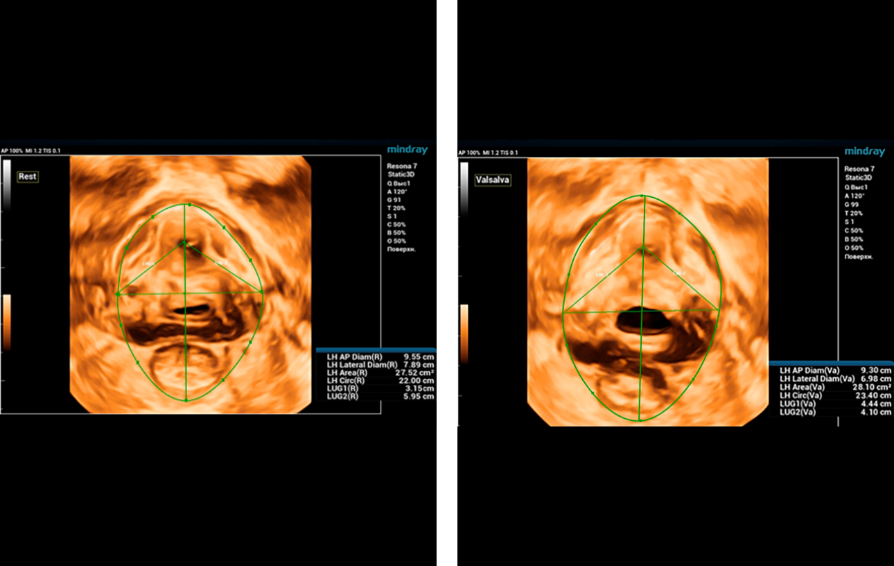

Mindray commenced its first #Nuewa Club Meeting in Bucharest, Romania!

Bajo el tema ŌĆ£inspirando el cuidado de la salud de la mujerŌĆØ, se llev├│ a cabo en la Ciudad de Panam├Ī la primera conferencia de Nuewa Club en Latino America.?